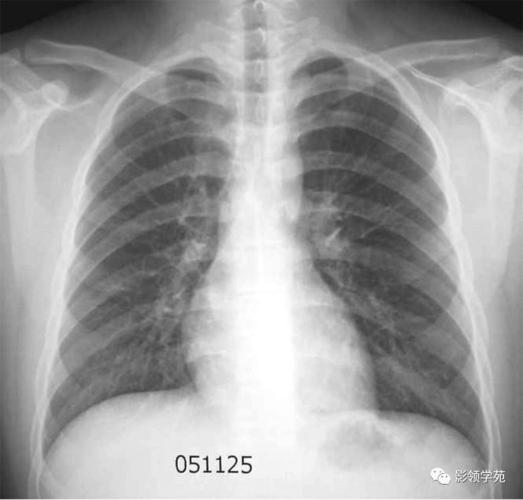

2.小叶性肺炎 表现为肺纹理增多,模糊.

小叶性肺炎表现为沿肺纹理分布的斑片状模糊致密影,密度不均,多发

小叶性肺炎的x线表现

小叶性肺炎x线

小叶性肺炎x线图片

小叶性肺炎胸片